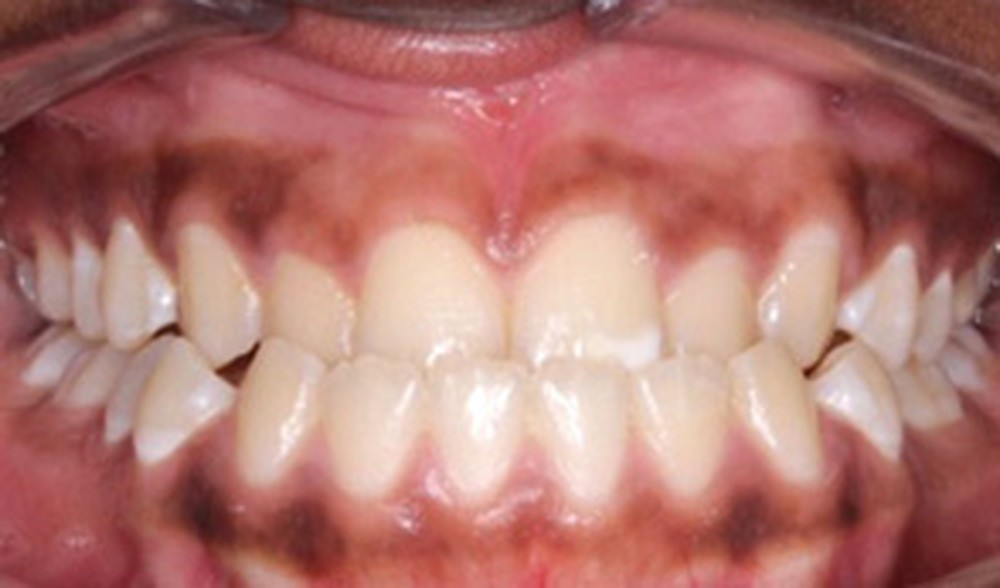

Examen clinique (fig. 1a-h)

À l’examen de face, Anisa présente un visage ovalaire, des hémifaces symétriques, des lignes horizontales parallèles, une augmentation de l’étage inférieur, une occlusion labiale légèrement forcée et des dents mandibulaires exposées au sourire. Les profils général et sous-nasal sont concaves avec un angle naso-labial augmenté et une prochéilie inférieure.

L’examen clinique endo-buccal révèle une denture adulte jeune avec un inversé d’articulé antérieur de 13 à 23, des tatouages gingivaux ethniques et des taches de décalcifications, un parodonte sain mais un brossage insuffisant.

L’arcade maxillaire est en V et la voûte palatine profonde. L’arcade mandibulaire a une forme en U (non-concordance des formes d’arcade) et présente des malpositions des dents cuspidées. La médiane mandibulaire est décalée à gauche de 2 mm ; le recouvrement antérieur est de 2 mm ; les molaires sont en classe III avec un surplomb inversé.